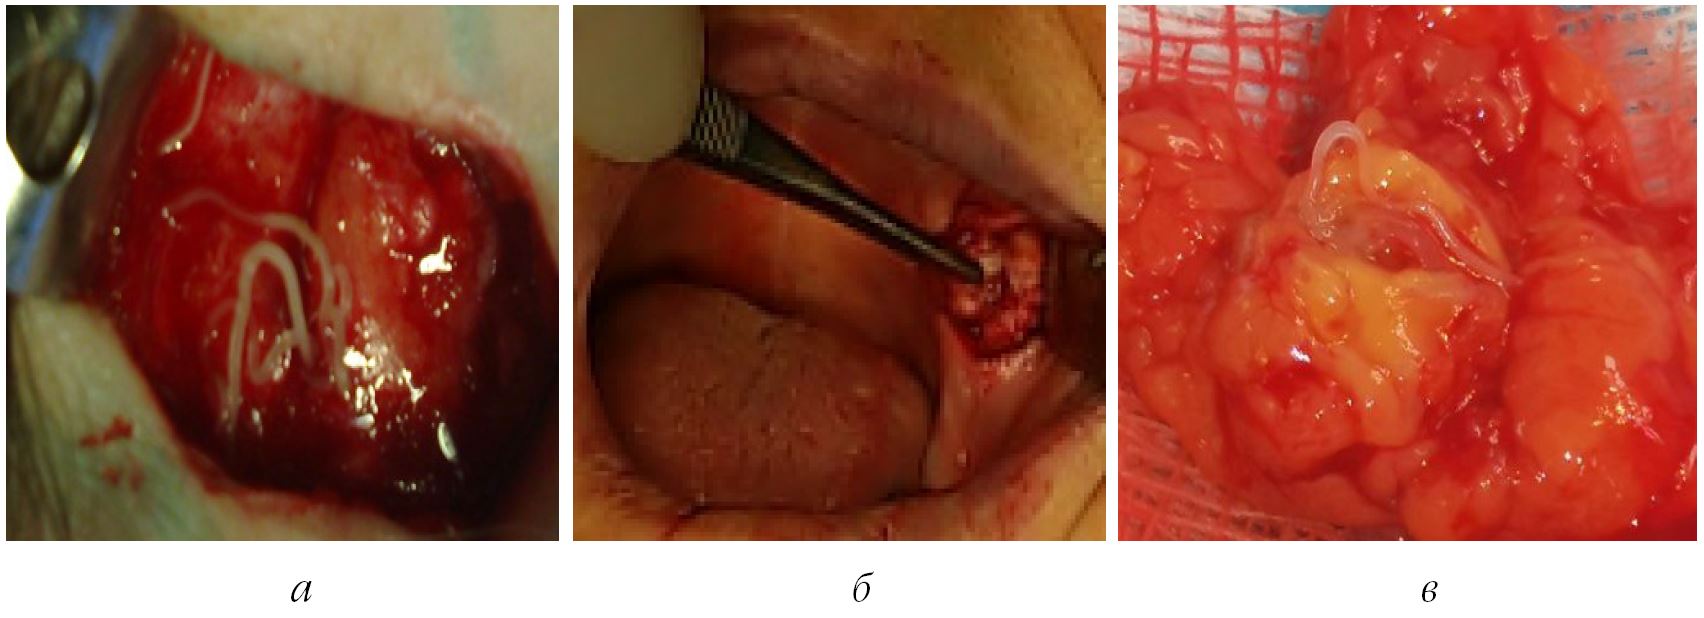

В результате интраоперационного обнаружения капсулы со специфическим содержимым (рис. 2, а, б) проводили коррекцию формулировки основного диагноза на «дирофиляриоз, инкапсулированная форма», выполняя все определенные эпидемиологическим регламентом действия.

Возвращаясь к диагностическим казусам, необходимо упомянуть еще об одном клиническом наблюдении. У девочки 15 лет был диагностирован хронический лимфаденит подчелюстной области справа, который сопровождался периодическими болями на

протяжении 4 месяцев. Эти боли возникали спонтанно и исчезали после курса антибактериальной терапии. Однако через месяц после купирования последнего обострения симптомы вернулись, и пациентка обратилась за консультацией. В ЧЛХ КСБ ПГМУ проведена эксцизионная биопсия, в результате которой обнаружена и удалена капсула с выявлением живого гельминта длиной 10 см (рис. 2, в).

Рис. 2. Локализация гельминта в челюстно-лицевой области: а ‒ гельминт в височной области справа; б ‒ капсула гельминта в щечной области слева; в ‒ вид удаленной капсулы с живым гельминтом